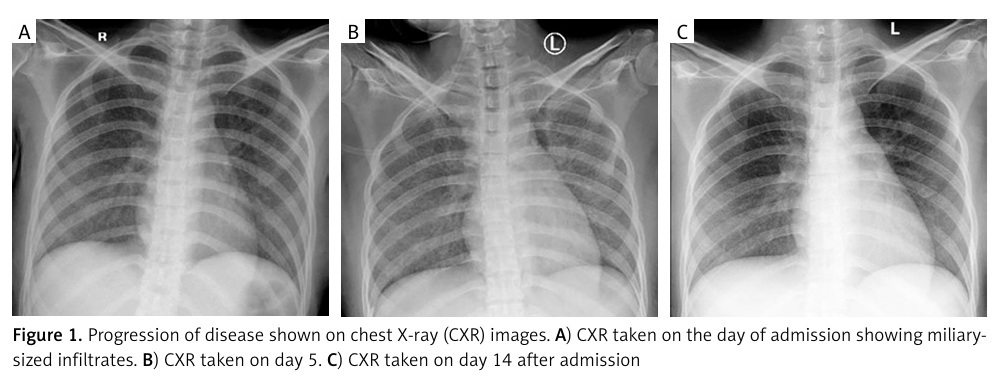

Here, we reported a case of an opportunistic infection mimicking COVID-19 in a TB/HIV-infected patient. A 22-year-old female presented to our hospital with decreased consciousness, shortness of breath, and cough. Lab results showed lymphocytopenia and thrombocytopenia as well as elevated C-reactive protein, D-dimer, and ferritin, which is classically suggestive of COVID-19 infection. She was diagnosed with probable COVID-19, but two subsequent consecutive RT-PCR tests for SARS-CoV-2 were negative. Both sputum GeneXpert MTB rapid molecular test and HIV immuno-serology rapid test were positive, and chest X-ray showed bilateral miliary infiltrates. Therefore, the patient was diagnosed as TB/HIV with secondary opportunistic infection.